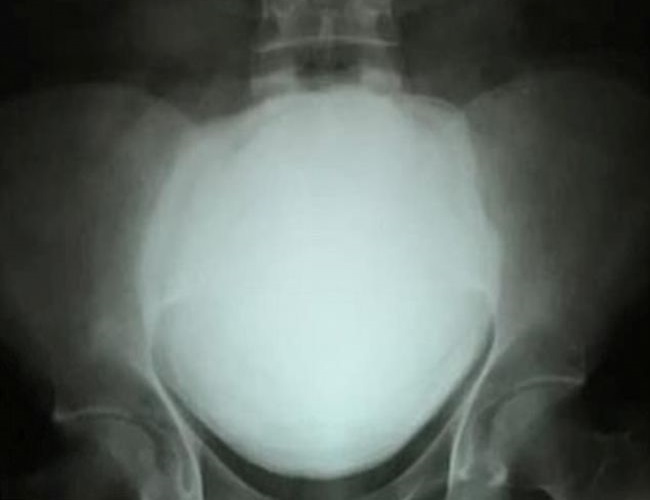

gif_animation おそらく「今まで発見された中でも最大級であろう」とされる尿路結石(膀胱結石)がインドの男性の体から摘出された。重さ1.4kg、恐ろしい痛み…。[6]img